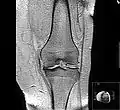

Diagnosis is made with reasonable certainty based on history and clinical examination.[41][42] X-rays may confirm the diagnosis. The typical changes seen on X-ray include: joint space narrowing, subchondral sclerosis (increased bone formation around the joint), subchondral cyst formation, and osteophytes.[43] Plain films may not correlate with the findings on physical examination or with the degree of pain.[44] Usually other imaging techniques are not necessary to clinically diagnose osteoarthritis.

MRI of osteoarthritis in the knee, with characteristic narrowing of the joint space.

Primary osteoarthritis of the left knee. Note the osteophytes, narrowing of the joint space (arrow), and increased subchondral bone density (arrow).